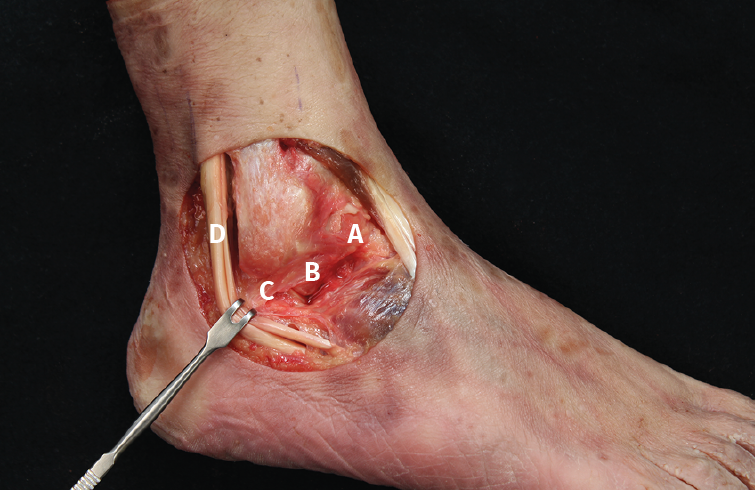

Figura 2. Anatomía del complejo lateral del tobillo. A: fascículo superior del ligamento talofibular anterior (LTFA); B: fascículo inferior del LTFA; C: ligamento calcaneofibular (LCF);  D: tendones peroneos.

1. Inicialmente, con los ligamentos íntegros (Figura 2), realizamos las maniobras anteriormente mencionadas (CA, EV) y registramos la movilidad angular detectada por el sensor en los 3 planos espaciales.